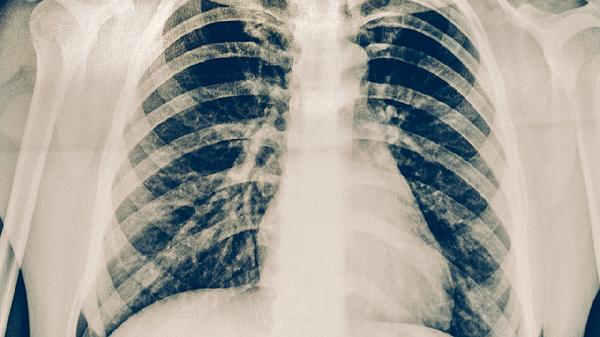

胸部X線或CT檢查可發(fā)現(xiàn)肺結(jié)核特征性改變,如上肺野浸潤(rùn)影、空洞形成或纖維鈣化灶。影像學(xué)能評(píng)估病變范圍與嚴(yán)重程度,但對(duì)不典型病例鑒別診斷價(jià)值有限。活動(dòng)性肺結(jié)核常見多形態(tài)混合病灶,需與肺炎、肺癌等疾病鑒別。兒童肺結(jié)核可能僅表現(xiàn)為肺門淋巴結(jié)腫大,需特別注意。